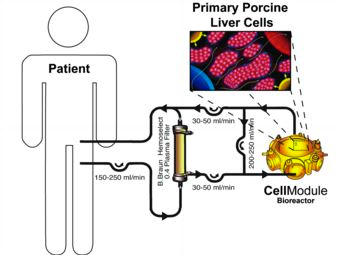

The objective of this study was to evaluate the feasibility and safety of a hybrid liver support system with extracorporeal plasmaseparation and bioreactor perfusion in patients with acute liver failure (ALF) who had already fulfilled the criteria for high-urgency liver transplantation.

8 patients (1 male, 7 female) were treated in terms of bridging to transplantation. The mean age was 36.5 years (range 20-58). Etiology of liver failure was drug-related (n=2), hepatitis B infection (n=3), and unknown for three patients. The bioreactors were charged with primary liver cells from specific pathogen-free pigs. Cell viability varied between 91 and 98%.

Continuous liver support treatment over a period of 8-46 hours (mean 27.3 h) was safely performed and well tolerated by all patients. No complications associated with the therapy were observed during the follow-up period. Thrombocytopenia was considered to be an effect of the plasmaseparation. Subsequently, all patients were transplanted successfully and were observed over at least two years with an organ and patient survival rate of 100%. Screening of patient’s sera for antibodies specific for porcine endogenous retroviruses (PERVs) showed no reactivity - either prior to application of the system, or after extracorporeal system.

The results encourage us to continue the development of the technology, and further studies appear to be justified. The bioreactor-technology has been integrated into a modular extracorporeal liver support (MELS) system, combining biologic liver support with artificial detoxification technology.